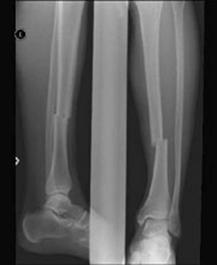

Fracturi simple: SPIRALA OBLICA TRANSVERSALA

Fractura spirala de Fractura transversa de diafiza femurala Fractura spirala de diafiza tibiala

diafiza humerala

Fractura spirala de diafiza tibiala Fractura oblica de diafiza tibiala Fractura transversala de diafiza tibiala